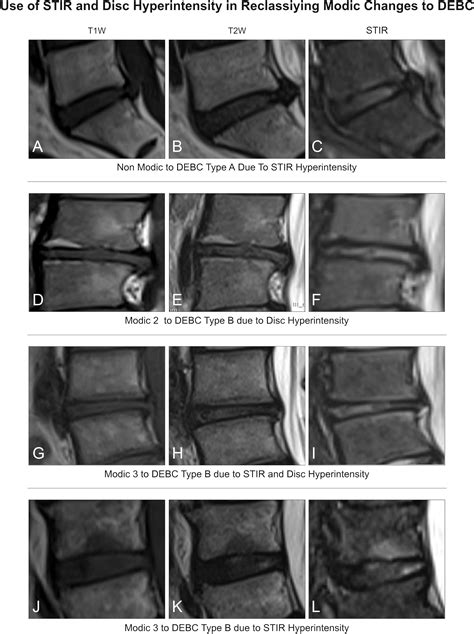

Modic changes are MRI-visible changes in the vertebral endplates—the bony interface between the intervertebral disc and the adjacent vertebral body. Named after Dr. Michael Modic, who first described these patterns in the late 1980s, they are classified into three types based on their appearance on T1 and T2-weighted MRI images. Modic Type 1 Endplate Changes are particularly notable because they represent an active, inflammatory process.

When you look at an MRI report, a radiologist describes these changes based on how the bone marrow reacts to the stress and degeneration of the spine. Type 1 changes are often characterized by:

• Bone Marrow Edema: The presence of excess fluid in the bone marrow, indicating acute inflammation.

• Vascularization: Increased blood flow to the area as the body attempts to repair the damaged endplate.

• Fibrosis: Replacement of normal bone marrow with fibrous tissue.

Unlike Type 2 changes (which show fatty replacement) or Type 3 changes (which show bone sclerosis), Type 1 is clinically significant because it is highly correlated with the presence of pain.

Modic Type MRI Signal Appearance (T1/T2) Pathology

Type 1 Low T1 / High T2 Inflammation / Edema

Type 2 High T1 / High or Iso T2 Fatty Replacement

Type 3 Low T1 / Low T2 Bone Sclerosis

Diagnosing Modic Type 1 Endplate Changes requires high-quality MRI imaging. Because these changes involve fluid and bone marrow, standard X-rays or CT scans are generally insufficient to see the soft-tissue-like inflammation. An MRI provides the necessary detail to differentiate between the active inflammatory state of Type 1 and the more stable, chronic states of Types 2 and 3.

Physicians will typically look for a "bright" signal on T2-weighted images and a "dark" signal on T1-weighted images at the level of the disc space. While these findings are objective, it is essential for clinicians to correlate these images with the patient's physical symptoms. In some cases, Modic changes can be found in asymptomatic individuals, so a comprehensive clinical exam is always required.